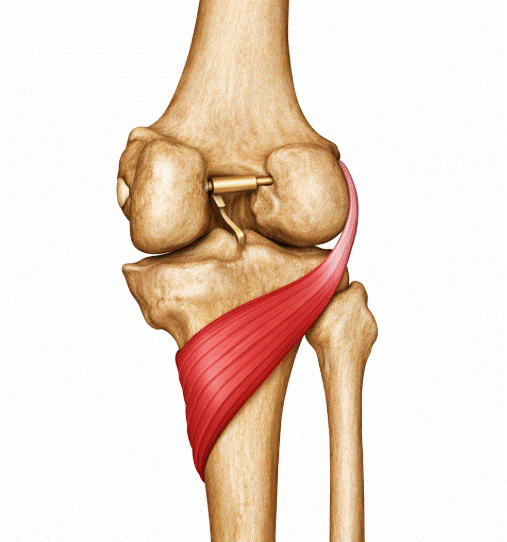

Lesiones en corredores populares: fuerza y prevención

Las lesiones en corredores populares son uno de los motivos de consulta más frecuentes en fisioterapia deportiva, y paradójicamente uno de los más prevenibles. El running ha experimentado un crecimiento exponencial en los últimos años, con millones de personas incorporando la carrera a su rutina de ejercicio sin una preparación física complementaria adecuada. Esta combinación […]